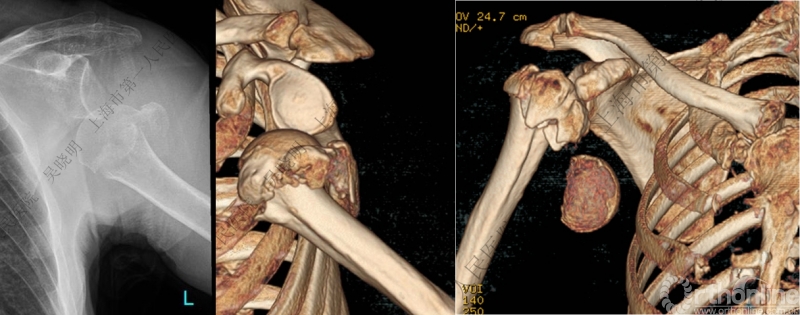

警惕孤立性向下移位的大结节骨折

X线是孤立性向下移位的大结节,一定要小心,多伴有肱骨外科颈骨折

肱骨解剖颈伴大结节骨折的老年性肩关节前脱位

切开复位

闭合复位

全麻下闭合复位,钢板固定